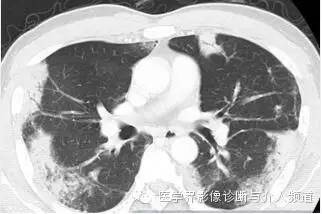

男,54岁,发烧咳嗽2周。

初始胸片示两肺野多灶性斑片影,其中两肺上野靠近外周可见边界欠清的实变影,这是典型的慢性嗜酸性粒细胞性肺炎“肺水肿反转影”的表现。CT示两肺叶多灶性非节段性实变影,病变以两上肺周围性分布为主。

CEP的典型影像学表现:普通X线平片为非节段性、分布广泛互相融合的肺泡及间质性实变,病变以中上肺周围性分布为主,表现为“肺水肿反转影”。CT或HRCT表现为一侧或两侧融合性实变、斑片状实变、磨玻璃影、条带状致密影,实变灶与正常肺组织的分界截然清楚。此种典型征象并非见于所有CEP病例。